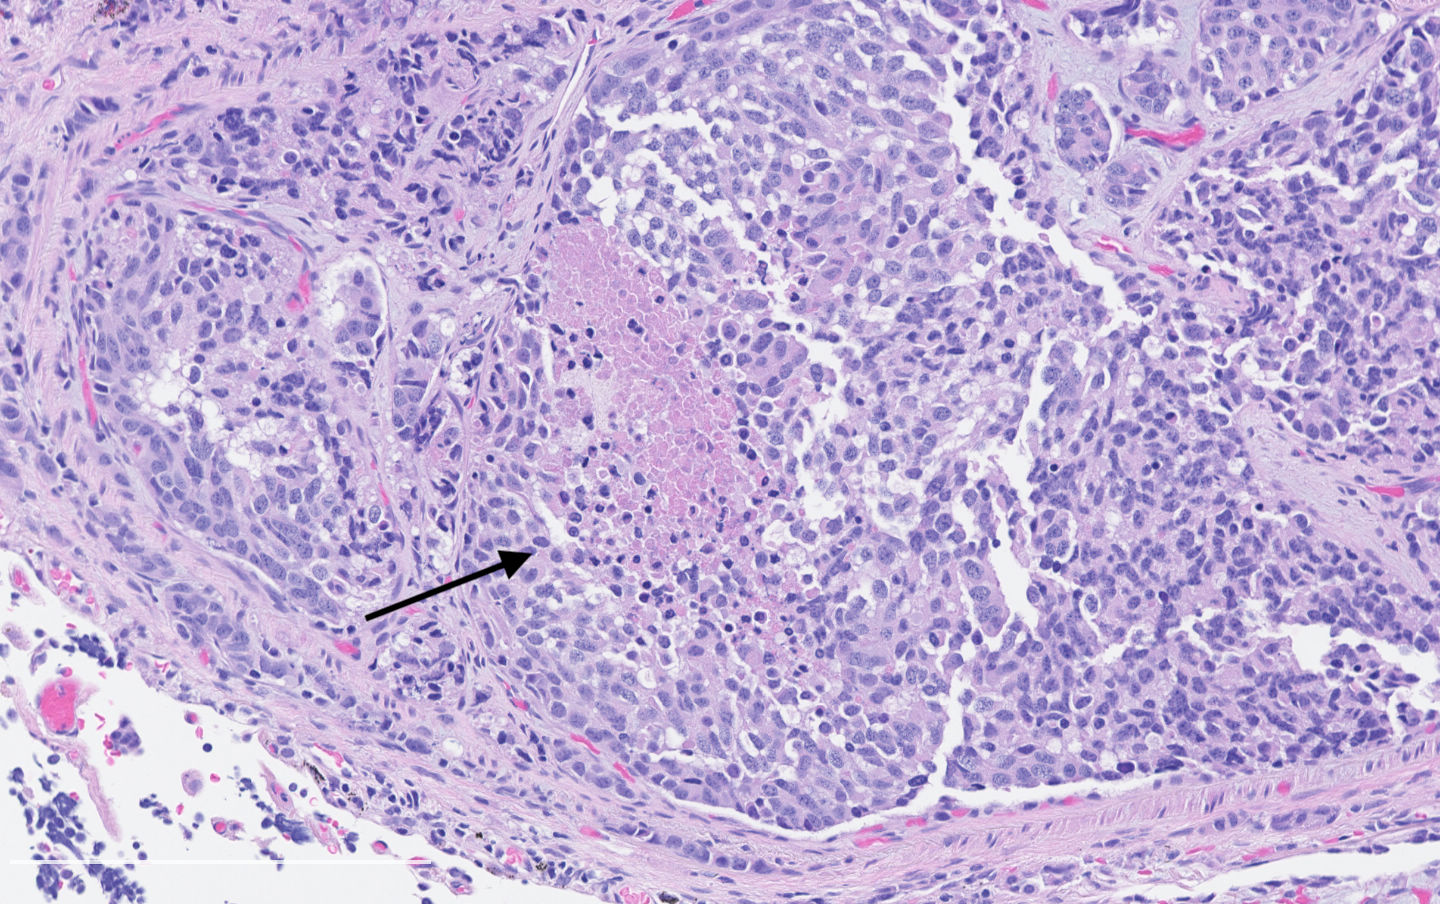

- Diagnostic criteria:

- Neuroendocrine morphology with 2 - 10 mitoses per 2 mm² or presence of necrosis

- Necrosis can be in large zones but is usually punctate

- Mitotic rate should be counted in the area with the highest proliferation rate (hot spot)

- Neuroendocrine morphology with 2 - 10 mitoses per 2 mm² or presence of necrosis

- Neuroendocrine histologic patterns similar to typical carcinoids: organoid, trabecular, rosette formation, papillary, pseudoglandular, follicular

- Tumor cells are as typical carcinoid: uniform with a polygonal shape, round to oval nuclei with salt and pepper chromatin and inconspicuous nucleoli, along with moderate to abundant eosinophilic cytoplasm

- Greater pleomorphism than for typical carcinoid is common (Arch Pathol Lab Med 2010;134:1628)

- Stroma is fine and highly vascularized; hyalinization, cartilage or bone formation are possible

Contributed by Philippe Joubert, M.D., Ph.D.